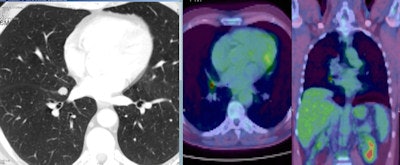

A 56-year-old man with a small nodule identified at low dose CT scan between the middle and right lower lobe. PET scan shows a high FDG uptake. A robotic segmental resection of the nodue was performed with a frozen section that showed a small cell lung cancer. Patient was treated with chemo and radiotherapy with success. Image courtesy of Dr. Giulia Veronesi.

A 56-year-old man with a small nodule identified at low dose CT scan between the middle and right lower lobe. PET scan shows a high FDG uptake. A robotic segmental resection of the nodue was performed with a frozen section that showed a small cell lung cancer. Patient was treated with chemo and radiotherapy with success. Image courtesy of Dr. Giulia Veronesi.The study authors, led by Dr. Giulia Veronesi, director of the Lung Cancer Early Detection Unit at the European Institute of Oncology in Milan, noted that CT screening for lung cancer remains up for debate. Although the National Lung Screening Trial found that low-dose CT reduced lung cancer mortality by about 20%, the modality results in a high rate of indeterminate and false-positive nodules.